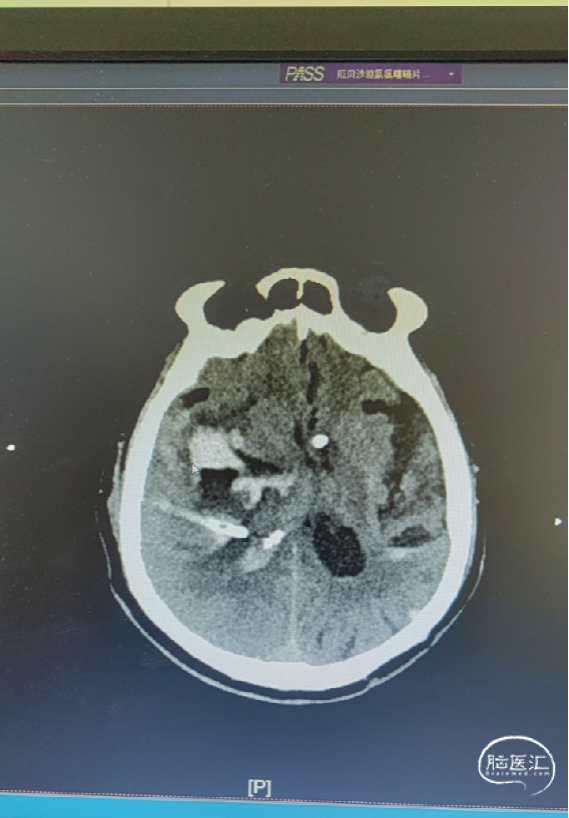

治疗:脑室穿刺,对侧脑血肿引流。

术后CT

手术过程

扫码观看手术视频